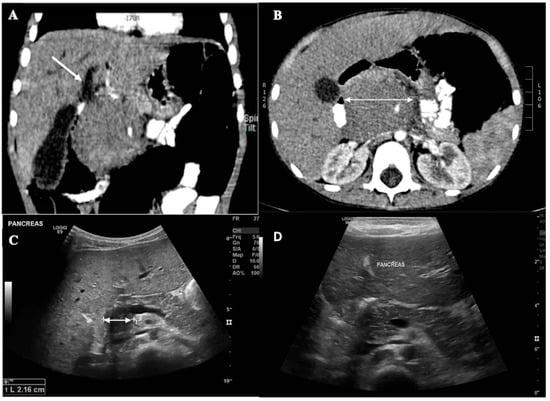

A 4-year-old boy, previously healthy, presented to a peripheral hospital with a 2-week history of progressive jaundice. His initial complete blood count at the referring hospital was reported as normal with no abnormal cells seen. He was initially diagnosed clinically with Hepatitis A and treated conservatively. No virology studies were reported at the time. However, his symptoms persisted over subsequent weeks, along with the development of fever, dark urine, pale stools, and severe pruritus. Physical examination revealed no palpable masses, lymphadenopathy, or hepatosplenomegaly. An abdominal ultrasound showed a mass at the peripancreatic head region causing biliary obstruction. Abdominal computed tomography showed a well-defined retroperitoneal mass which was displacing the pancreatic head anteriorly and compressing the common bile duct with biliary dilatation (Figure 1A,B).

We sought to relieve the common bile duct obstruction before starting chemotherapy. Endoscopic retrograde cholangiopancreatography (ERCP) was not available in the hospital, surgical intervention was associated with concerns of complications and delayed chemotherapy, and radiation therapy-associated complications outweighed the benefits. We, therefore, proceeded with systematic chemotherapy without a biopsy of the mass. The patient was started on induction therapy with ten days of full doses of Ara-C and five days of 50% dose reduction of etoposide. His bilirubin level gradually decreased after starting chemotherapy, reaching 4.6 mg/dL (79 μmol/L) by day 9 of treatment. He received 50% of the dose of daunorubicin on day nine and then full doses on days 10 and 11. He tolerated chemotherapy well, and his LFTs gradually improved. Bone marrow evaluation after the first cycle of chemotherapy showed that the patient was in remission with negative minimal residual disease. Sequential abdominal ultrasonography showed interval size regression of the mass (Figure 1C). Once the patient was due for the second induction cycle, his LFTs normalized, and he received full doses of chemotherapy. After the second induction cycle, an ultrasound showed complete resolution of the mass (Figure 1D). He completed chemotherapy smoothly with three cycles of consolidation and was in remission four years after therapy was completed.

Figure 1. (A,B): Axial and coronal contrast enhanced CT images of the abdomen show a well-defined large round homogenous mass at the region of the pancreatic head measuring 5.2 cm × 5.7 cm × 6.1 cm displacing adjacent structures and encasing superior mesenteric artery, with upstream biliary tree dilatation (arrow). (C): Greyscale axial ultrasound image at the level of pancreatic head after starting chemotherapy obtained on day 17 shows mass size reduction measuring 3.4 cm × 3 cm × 2 cm, with reduced upstream biliary tree dilatation. (D): Grey scale ultrasound image after induction 2 showed no songoraphic residual mass, with resolved biliary tree dilatation.